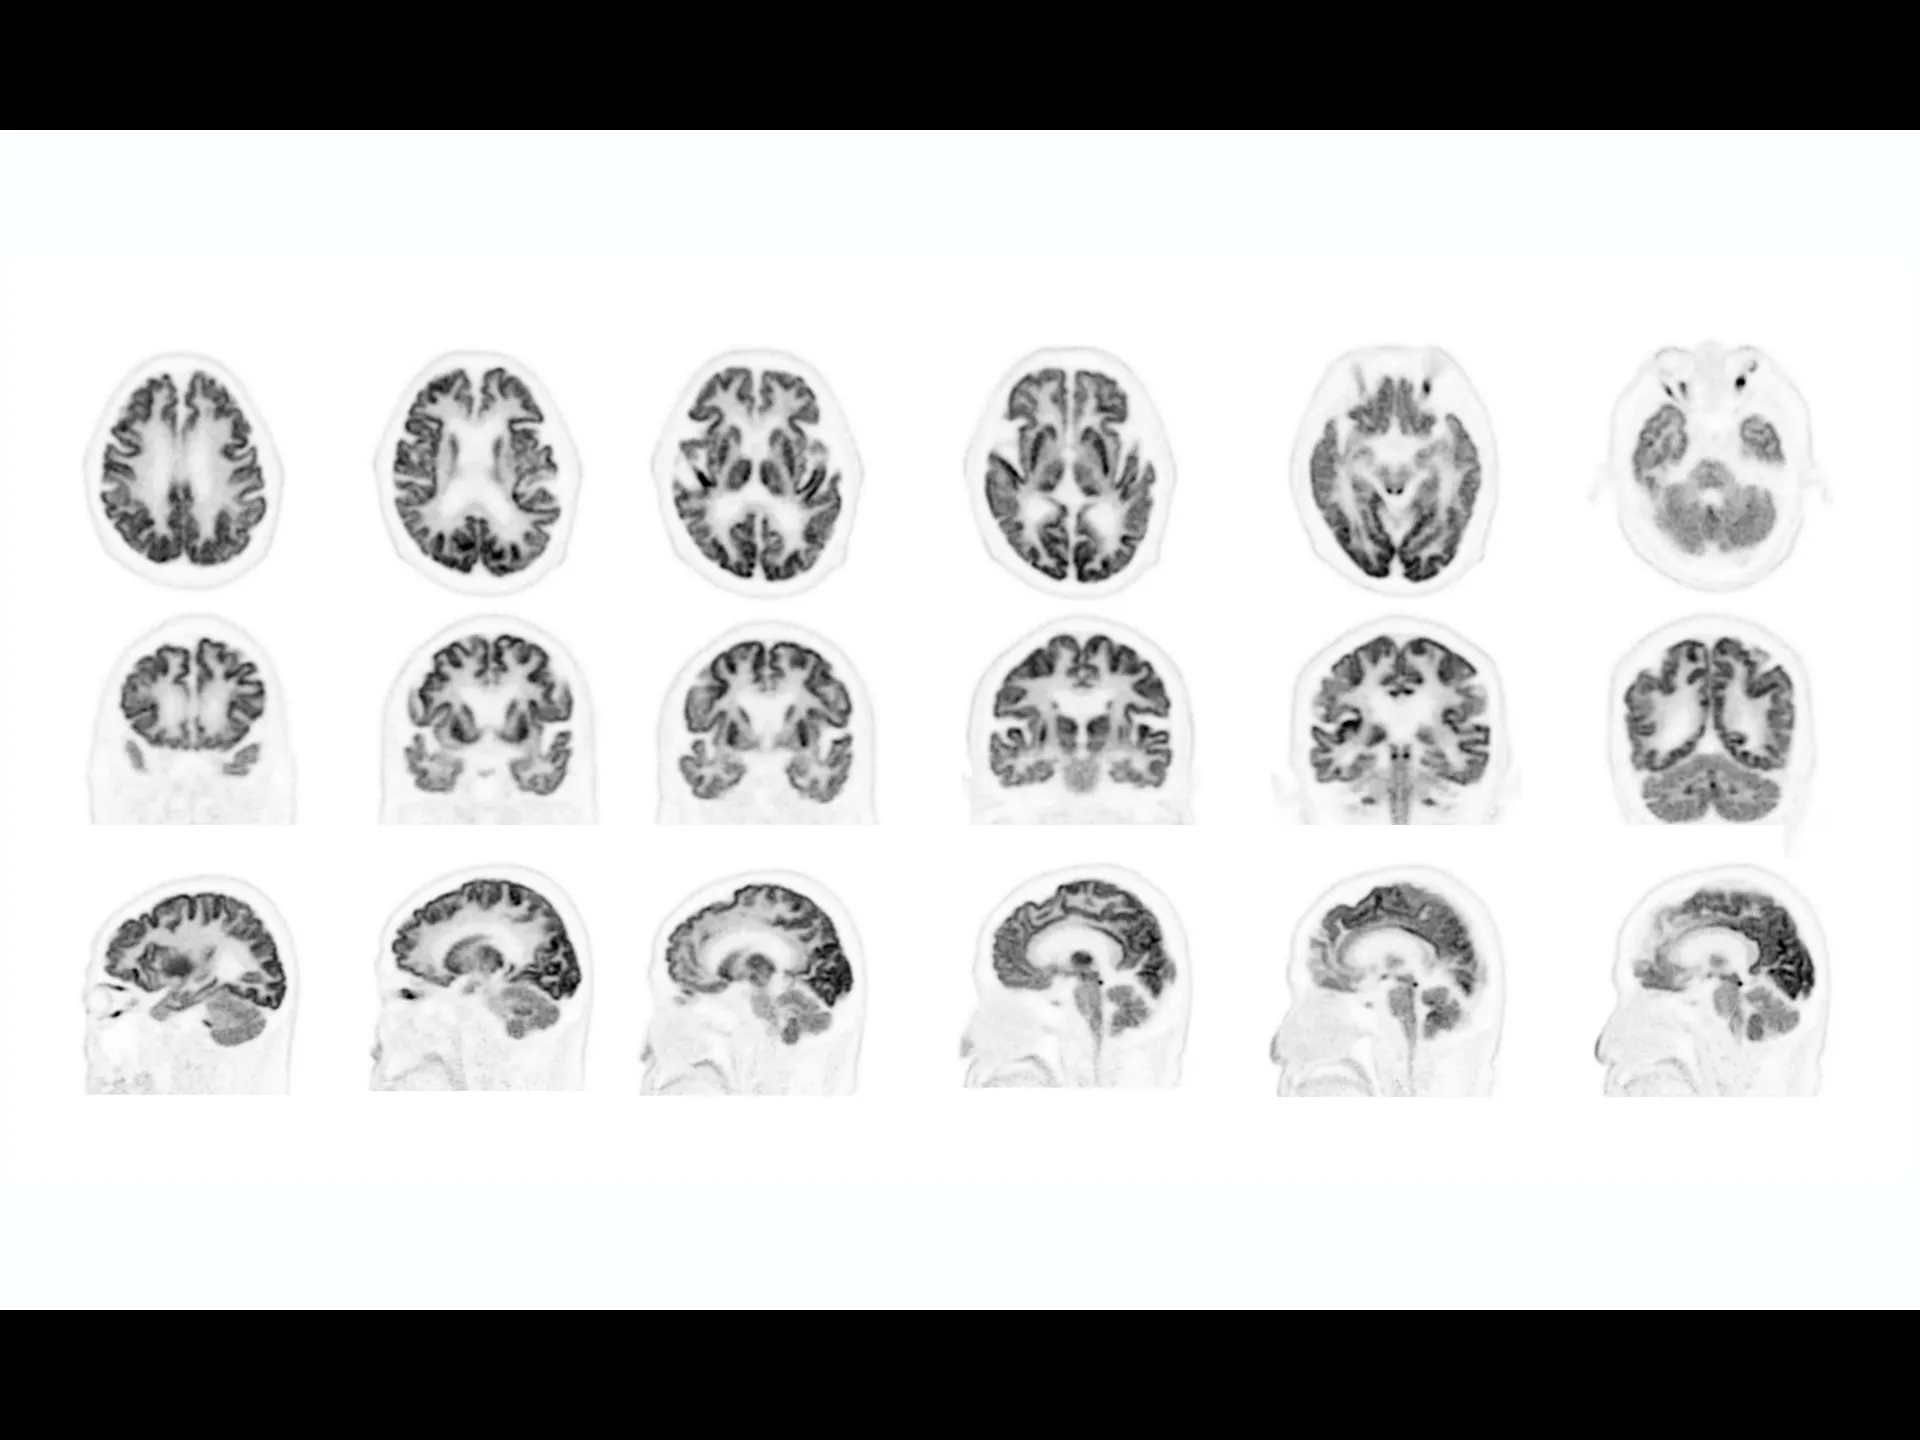

uMI Panvivo is a high performance PET/CT platform that moves state-of-the-art innovative advancement to clinical reality. It advances diagnostic precision with industry-leading NEMA spatial resolution of 2.9mm and time of fight (TOF) timing resolution of 219 picosecond (ps), while it’s air-cooled compact design make it more accessible to all. The human-centric design and fully AI-empowered workflow of uMI Panvivo deliver care to every patient while keeping the user in mind. Built on its scalable platform, uMI Panvivo’s powerful design builds the bridge toward long-term and sustainable success.

Driven by precision medicine and personalized care, uMI Panvivo offers the top-tier performance based on state-of-the-art detector technology and highly integrated system for better diagnostic confidence and capabilities.

Exceptional NEMA spatial resolution delivered by the finest crystal size of 2.76 mm in the industry.

Leading TOF resolution that boosts small lesion detectability and clarity.